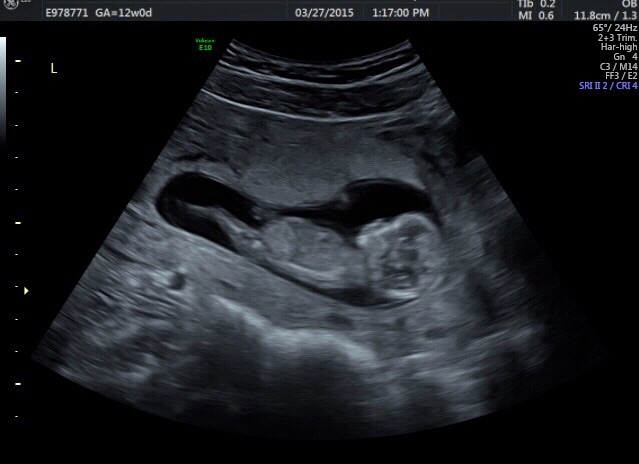

Here's our little love at 12 weeks! I can't get over how much he/she already looks like a 'real' person, can't wait for the next US when we find out the sex! So excited

We also graduated up one whole day! 12w 1d today.

12 week ultrasound